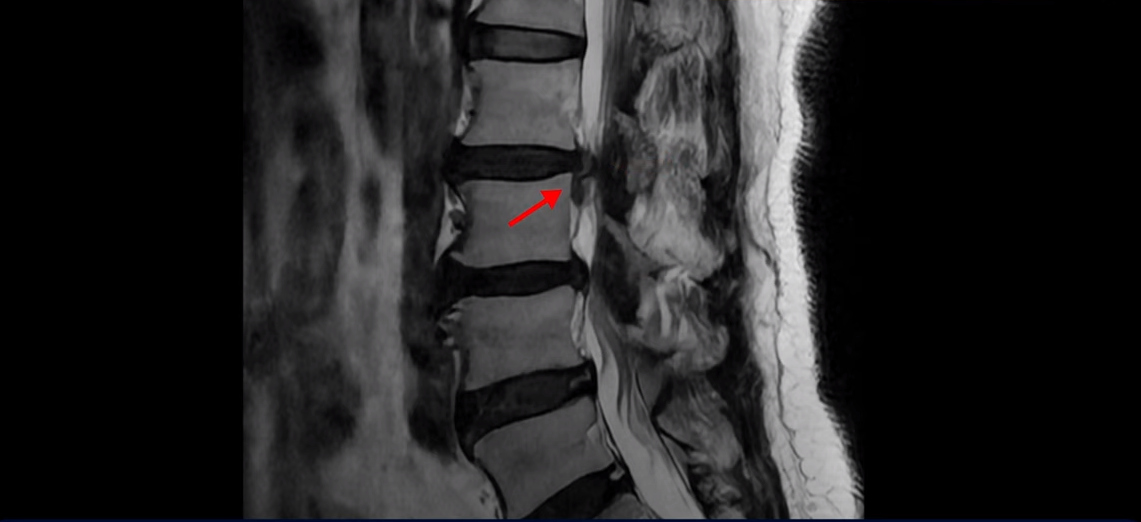

이분 MRI 보시면 2번 3번, 3번 4번이 두 마리가 특히 안 좋습니다.

2번 3번에는 우선 디스크가 파열되어 흘러내려 있습니다. 이 디스크는 파열된 지 오래된 걸로 보입니다.

이 마디는 중심성 협착도 있어서 허리 신경 공간이 많이 좁아져 있습니다.

3번 4번도 중심성 협착으로 신경 공간이 좁아져 있습니다.